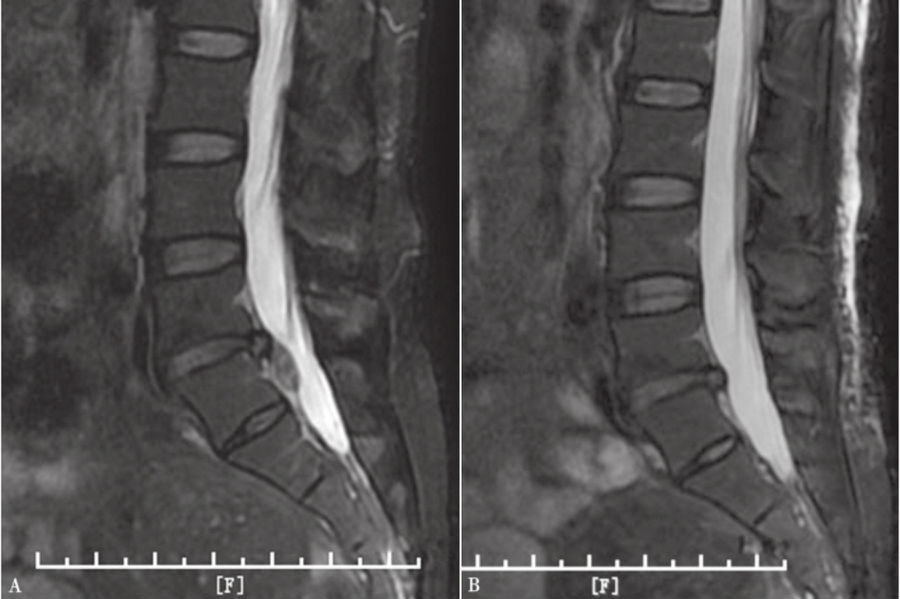

图44 术前和术后MRI核磁共振矢状位对比

A. 术前腰椎MRI矢状位;B.术后腰椎MRI矢状位